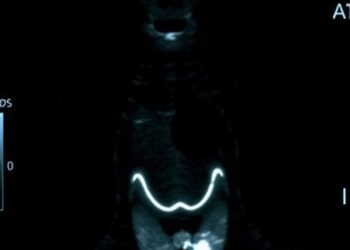

Ultrasound Nomogram Predicts Thyroid Cancer Spread

In recent advancements in the field of medical imaging and artificial intelligence, a groundbreaking study has emerged focusing on the ...